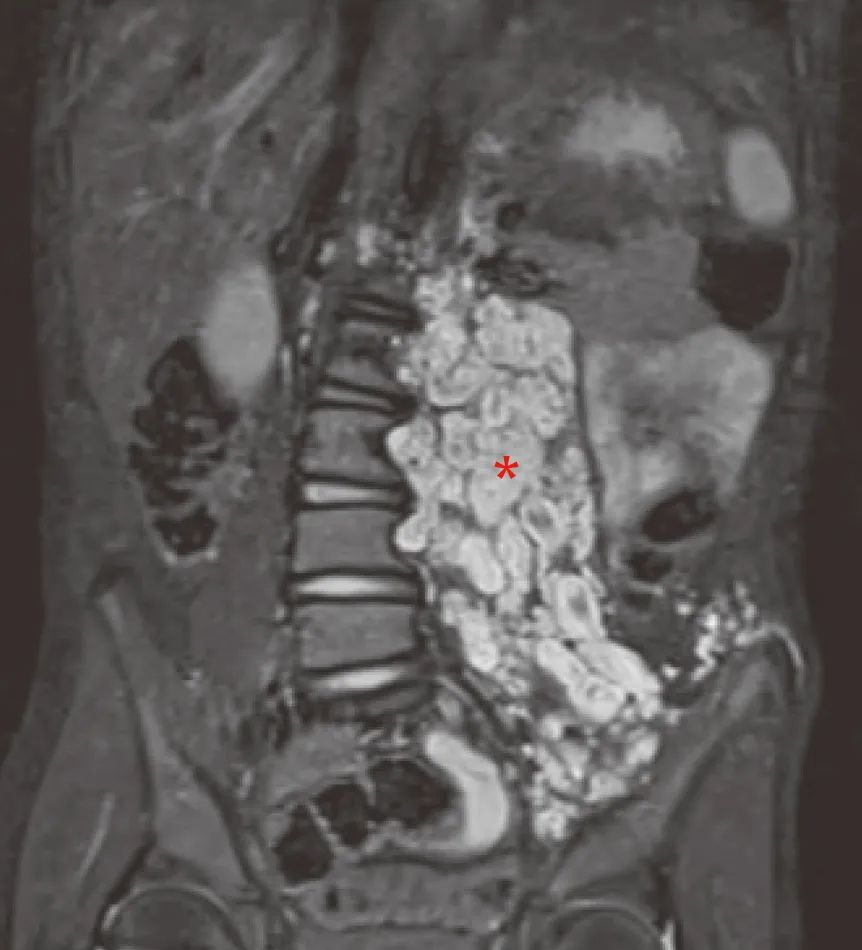

8岁男孩NF1-PN患者的核磁共振影像

(星号部位,源自文献:DOI: 10.1016/S1474-4422(14)70063-8)